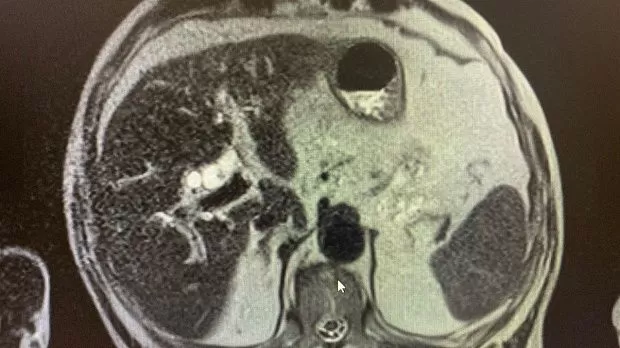

2)Биохимический анализ крови: Билирубин- 82,4 , прямой- 47,5 АЛТ- 92 , АСТ-136 , С-реактивный белок -44,4 скорость клубочковой фильтрации- 45 . МРТ: внутри- и внепеченочные протоки расширены , общий печеночный проток до 18 мм, холедох до 14 мм, в просвете конкременты до 14 мм. Заключение: Холедохолитиаз . Билиарная гипертензия.

На следующий день произведена ретроградная холангиопанкреатография.

Отмечатся юкстапапиллярное расположение большого дуоденального сосочка тип-3. Канюляция папиллотомом pull-type ,контрастирование водорастворимым контрастом .